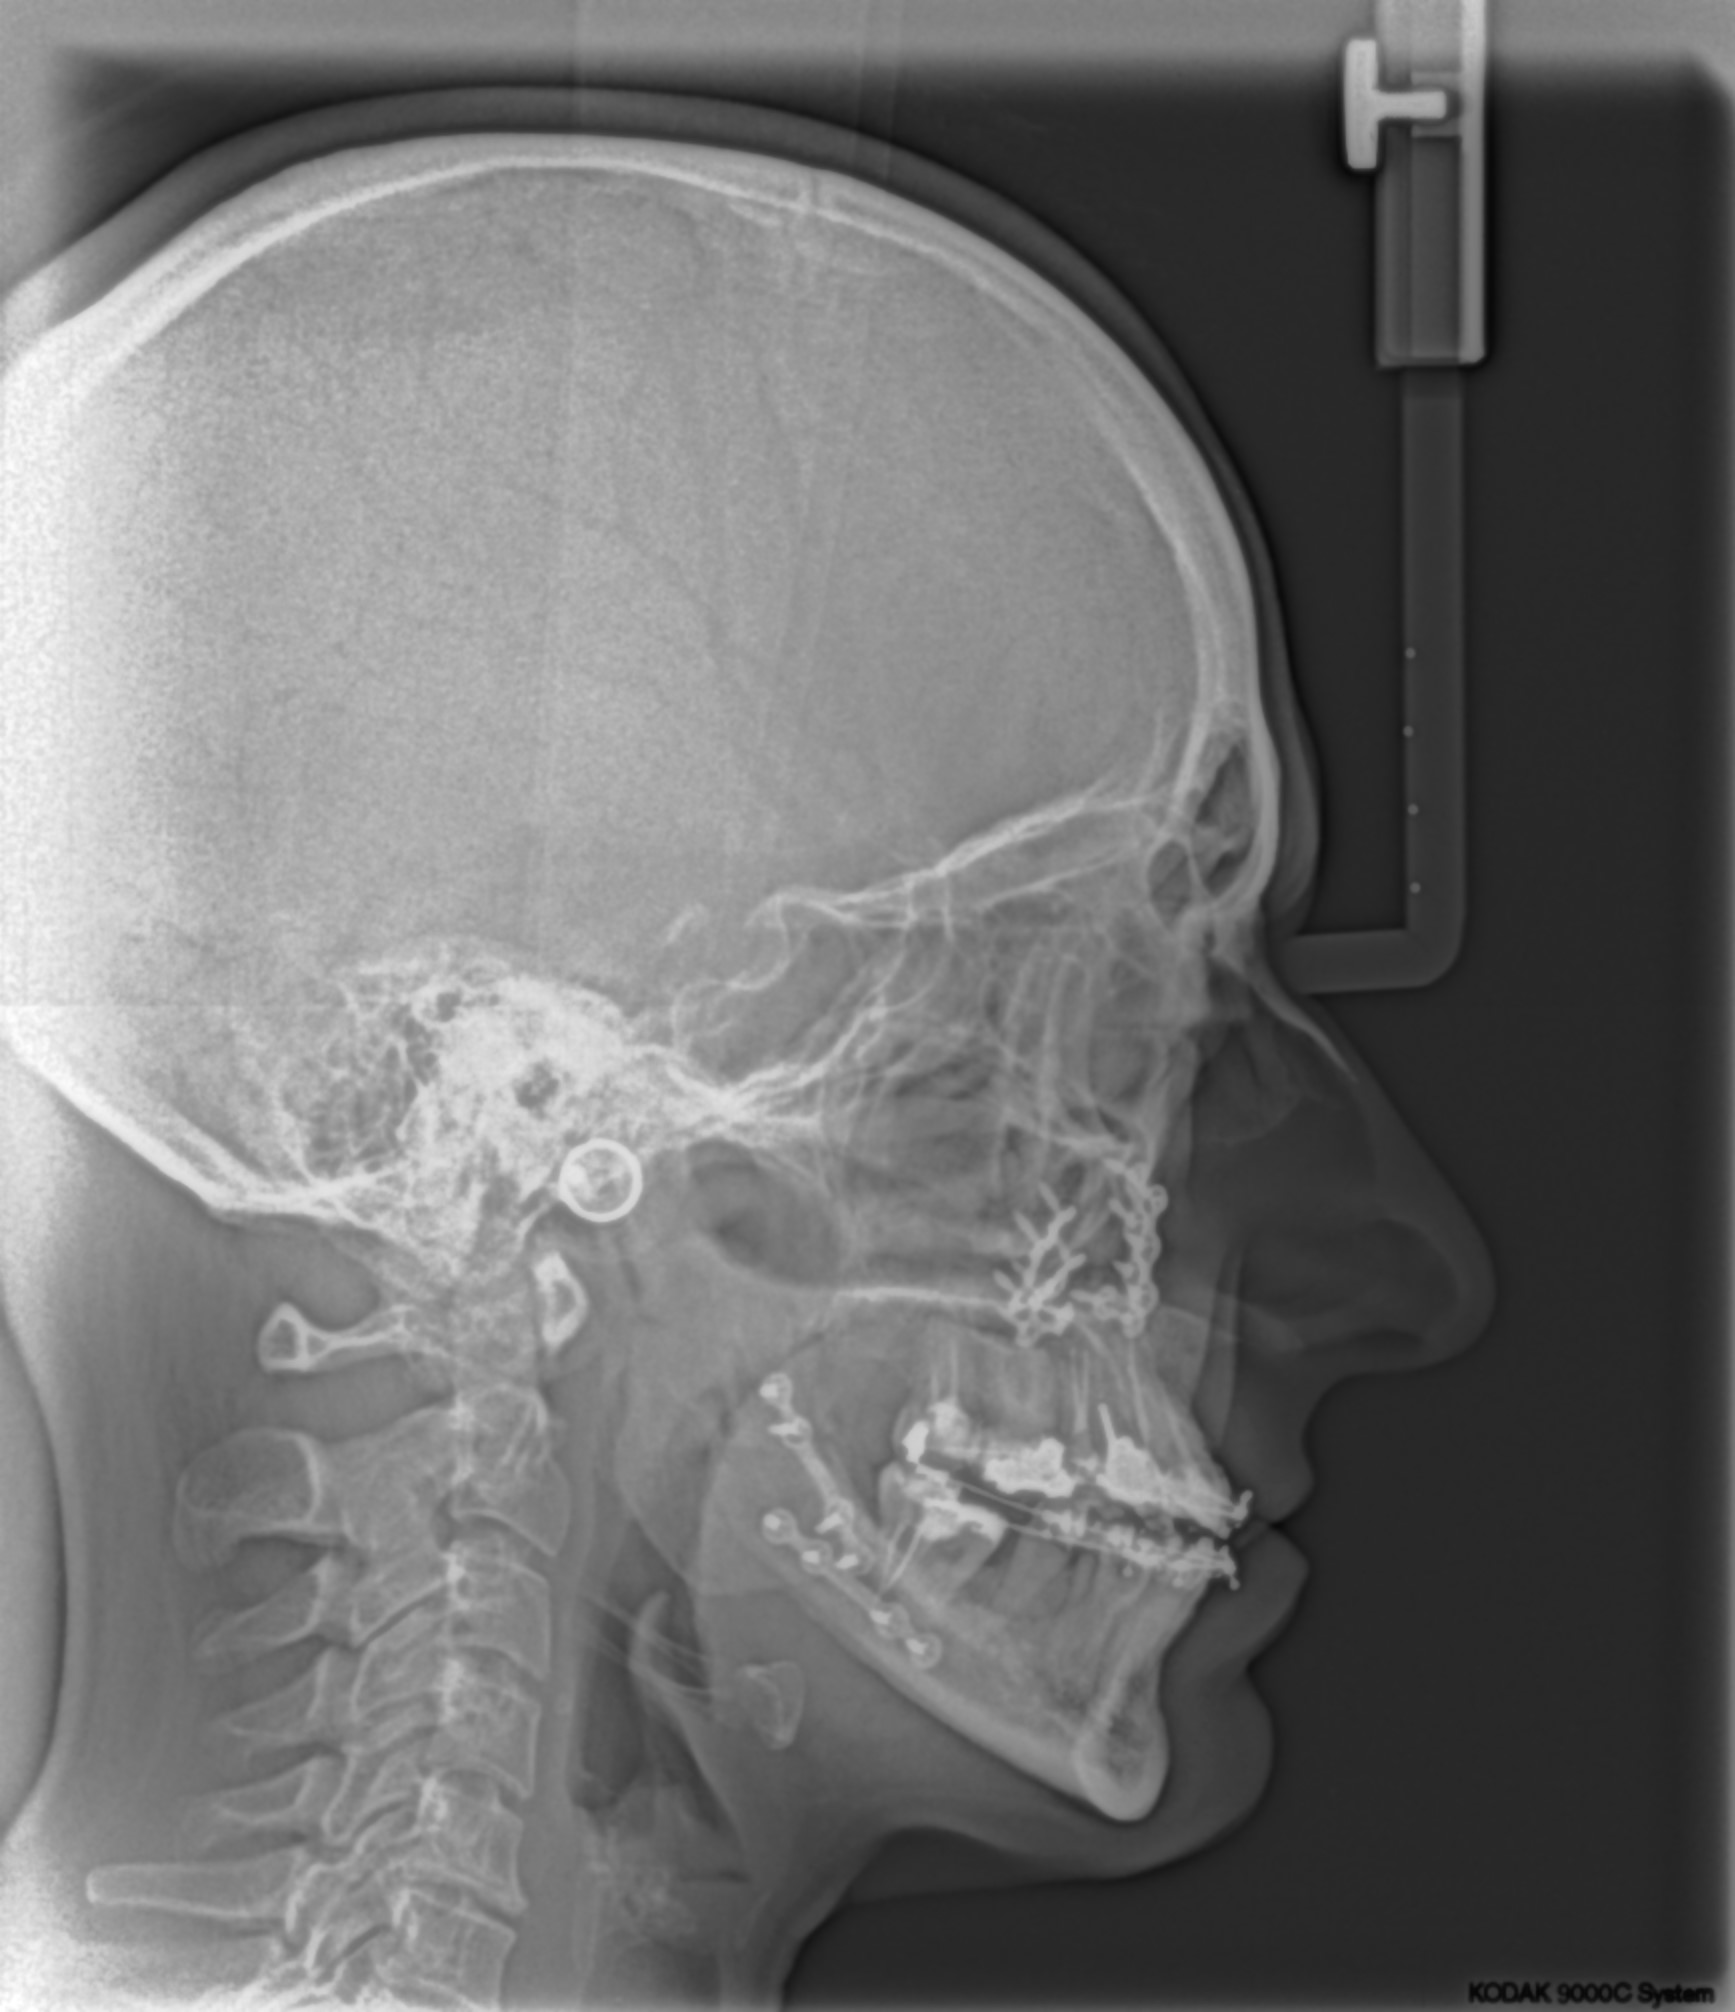

ΧΕΙΡΟΥΡΓΙΚΗ ΑΠΟΚΑΤΑΣΤΑΣΗ

Εφαρμόζεται σε ακραίες σκελετικές ανωμαλίες σε συνδυασμό πάντα με ορθοδοντική θεραπεία και σε συνεργασία με ειδικούς γναθοχειρουργούς με πολύ εντυπωσιακά και σταθερά ομολογουμένως αποτελέσματα.